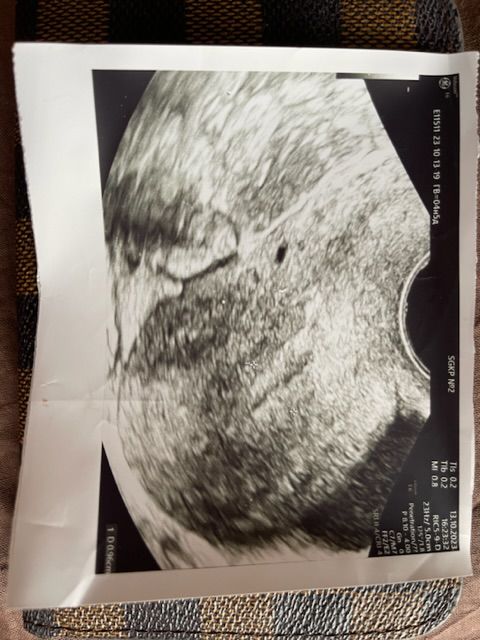

После больницы пошла опять в жк, кровь опять - , на узи анэхогенное образование в матке

На снимке узи написано ГВ=04н5д

Радом с анэхогенной зоной маленькая чёрная точка